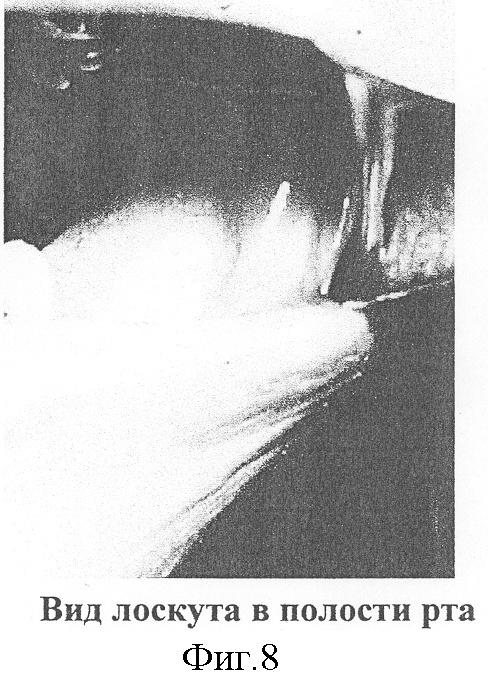

Фотографии пациента Е. на различных этапах лечения представлены на фиг.1-8.

13.04.03 г., больному проведена операция – верхняя шейная диссекция, после чего, через центральную мандибулотомию проведена резекция 1/2 языка и тканей дна полости рта. Выделена левая лицевая артерия и левая наружная яремная вена. В средней трети левого предплечья сформирован кожно-фасциальный лучевой лоскут в виде двух кожных элементов трапециевидной формы на общем основании из глубокой фасции предплечья. Размеры кожных элементов соответствовали размерам дефектов слизистой полости рта и языка и наружных покровов поднижнечелюстной области. Питающая ножка лоскута была представлена лучевой артерией и сопровождающими ее лучевыми венами. После мобилизации лоскута признаков нарушения кровоснабжения кожных элементов не отмечено. После пересечения сосудистой ножки лоскут был перенесен в зону дефекта и сложен пополам, кожными поверхностями наружу. Кожа лоскута, в месте сгиба, рассечена до фасциального основания. Листки глубокой фасции по периметру лоскута сшиты между собой, чтобы защитить сосудистую ножку от возможного инфицирования. Латеральный край одного из кожных элементов путем наложения трансоссальных швов фиксированы к внутренней поверхности тела нижней челюсти. Медиальный край сшит с краями слизистой языка и слизистой дна полости рта отдельными узловыми атравматическими кетгутовыми швами в два этажа. Края второго кожного элемента сшиты с краями кожи по периферии дефекта в поднижнечелюстной области. Ножка лоскута проведена под кожей на боковую поверхность шеи, где наложены микроанастомозы конец-в-конец между лучевой и лицевой артериями, а также между наружной яремной веной и лучевыми венами в месте их слияния. После пуска кровотока восстановилось кровообращение в лоскуте. После чего проведен остеосинтез нижней челюсти по линии центральной мандибулотомии титановой минипластиной. Раны в области реципиентных сосудов ушиты послойно. Донорская рана на предплечье закрыта расщепленными кожными лоскутами. В послеоперационном периоде признаков нарушения кровоснабжения лоскута и нагноения раны не наблюдалось. Назогастральный зонд удален на 9-е сутки, после чего больной питался естественным путем. Расщепленная кожа в донорской зоне прижилась полностью, функция предплечья и кисти не нарушилась. Больной выписан 27.04.03 г. Период стационарного лечения составил 14 койко-дней. Отмечен удовлетворительный функциональный и эстетический результат.